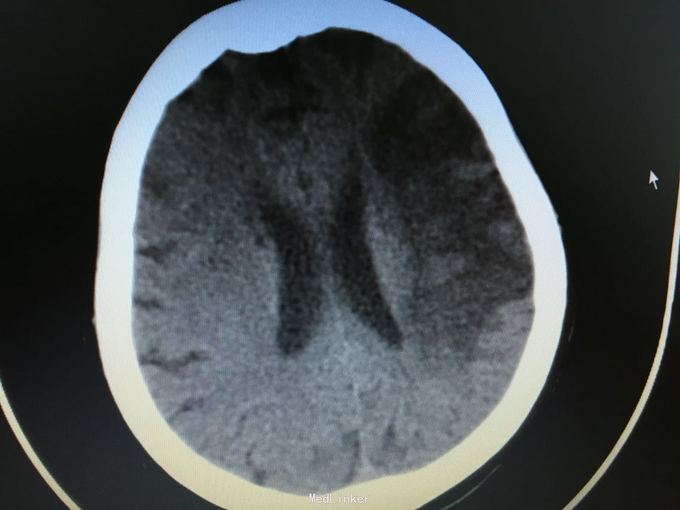

主诉:突发左侧肢体无力伴意识障碍2.5小时。 现病史:患者于2.5小时前突发左侧肢体无力,左侧肢体完全不能动,伴有意识障碍,急诊头CT显示多发脑梗死,为进一步诊治入院。 既往史:高血压,冠心病支架后,阵发房颤。

昏睡,完全混合性失语,双眼向左侧凝视,右侧肢体肌力0级,右侧病理征阳性。 头CT见多发陈旧小梗死。

诊断:大脑半球大面积脑梗死 治疗:抗血小板,脱水,降脂等,抗凝预防下肢静脉血栓

目前住院10余天,意识清楚,但仍遗留左侧肢体肌力0级,混合性失语等严重功能残疾。复查CT显示为左侧大脑半球大面积脑梗死。 讨论:对于高龄,大面积脑梗死患者,时间窗内是否溶栓?静脉还是动脉溶栓?